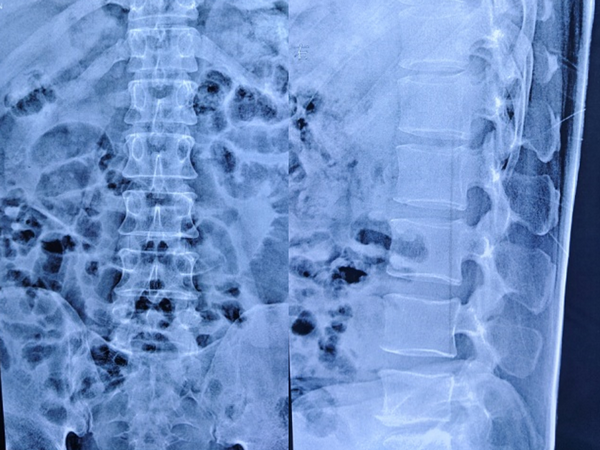

术前检查

检查提示腰5/骶1椎间盘向左后脱出,脊髓神经受压明显。骨科一病区徐明杰主任、王三木医师团队认真诊查病人,认为患者存在腰5/骶1椎间盘向左后脱出并椎管狭窄,保守治疗差,需要手术扩大狭窄的椎管并摘除突出的腰椎间组织解除神经受压,适合采用UBE技术为患者进行手术治疗。术前,徐明杰主任团队制定了严密的手术治疗方案,并与患者及家属充分、细致沟通。